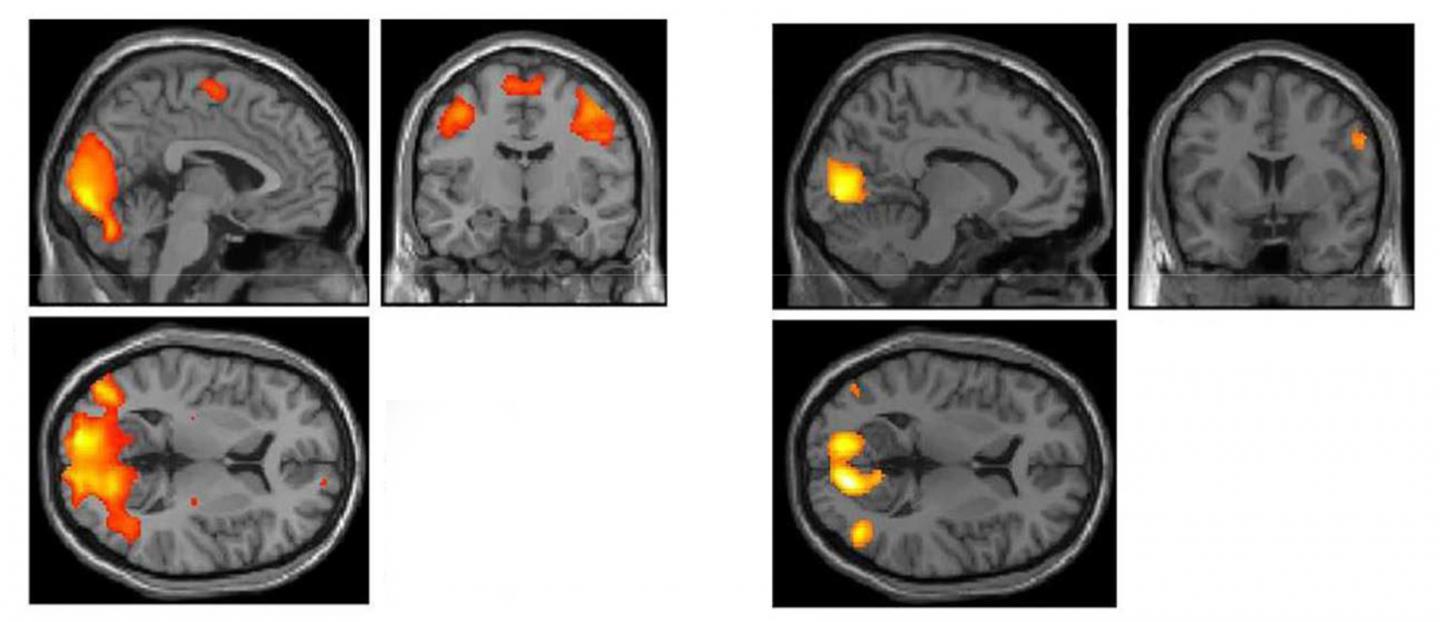

The differences in football players' versus cross-country runners' brains were specifically seen in regions of the brain responsible for visual processing. These regions were much more active in football players versus cross-country runners or volunteers who did not play college sports.

"We focused on these brain regions because physicians and trainers regularly encounter large deficits in players' ability to smoothly track a moving point with their eyes after suffering an acute concussion," Port said.